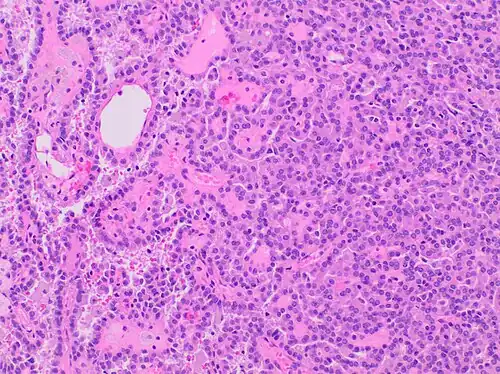

| Papillary renal cell carcinoma, type 1, characterised by tubulopapillary architecture with admixed foamy histiocytes in the papillary cores. | |

Type 1 PRCC, also known as a renal tumor caused by a genetic predisposition of hereditary papillary renal cancer syndrome, compromises approximately 25% of all PRCCs.[14][15] In the perspective of immunochemistry, it has a profile of strong CK7 and alpha-methyl acyl-CoA racemase (AMACR) expression at most focal CA-IX expression.[16] Histologically, its epithelium is composed of relatively small-sized simple cuboidal cells lined in a single layer.[17] These cells are well-characterized by basophilic cytoplasm.[18] Due to its solid growth, an extremely compact papillary architecture is often observed.[16] Other morphological characteristics include intracellular hemosiderin and foamy macrophages placed inside of papillary fibrovascular cores or psammoma bodies.[19] In general, the nuclei of type 1 PRCC belong to grade 1-2 of the Fuhrman system.[16]

A micrograph of type 1 PRCC, illustrating features of small basophilic cells with scarce cytoplasm. A single layer of cells are surrounding the basal membrane.[20] Foamy macrophages are inside of papillary fibrovascular cores.